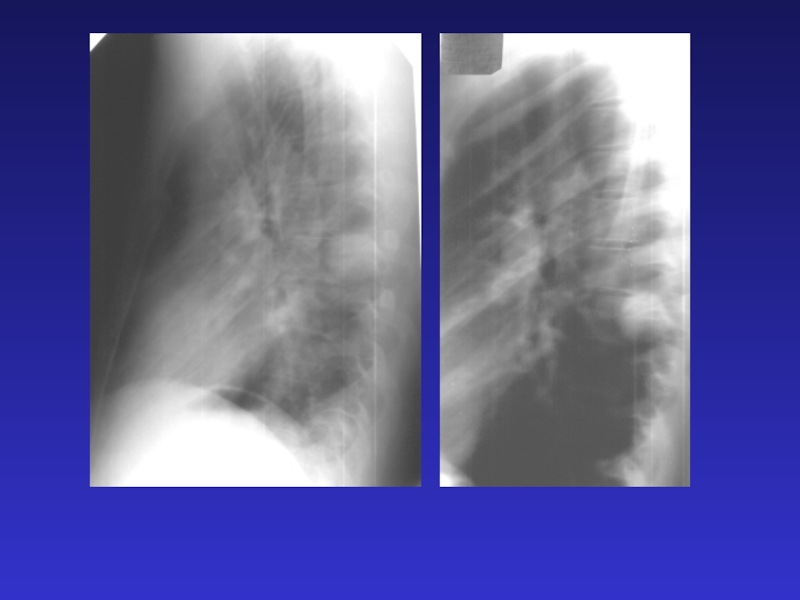

Рентгенография – основной метод исследования органов грудной клетки, используется при всех заболеваниях легких, сердца, позволяет также оценить гемодинамику малого круга кровообращения. Выполняется в стандартных проекциях (прямой и боковой)

Слайд 2Рентгенография – основной метод исследования органов грудной клетки, используется при

всех заболеваниях легких, сердца, позволяет также оценить гемодинамику малого круга кровообращения. Выполняется

в стандартных проекциях (прямой и боковой)

Рентгенография  – основной метод исследования органов грудной клетки, используется при всех заболеваниях легких, сердца, позволяет также